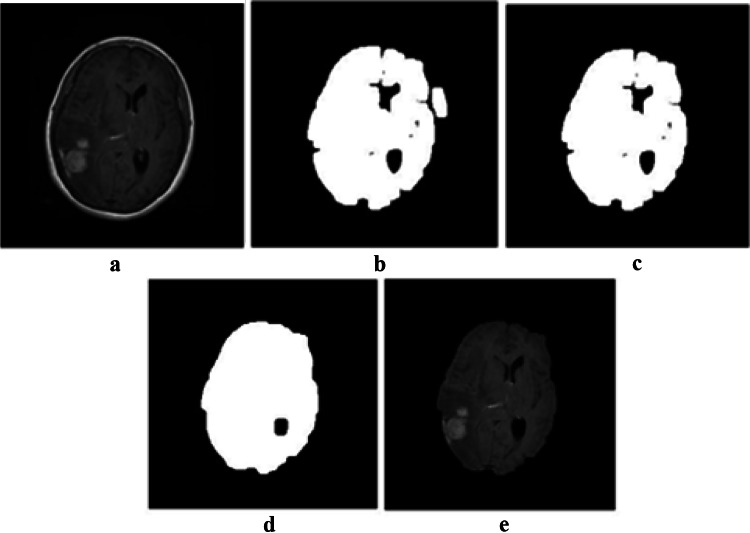

In the first step, after converting the image into a binary image, the opening operator with a disk structuring element is applied on the image to make sure that the skull and brain are not connected anymore. The opening operation erodes an image and then dilates the eroded image. The opening operation is beneficial for removing tiny objects from an image while preserving the shape and the size of the larger objects in the image. After that, the largest element of the image, i.e., the brain tissue, is selected. Next, the closing operator is applied to make sure the lost parts of the brain are reconstructed. The closing operation first dilates an image and then erodes the dilated image using the same structuring element. It is effective for filling small holes of an image while preserving the shape and the size of the objects in the image. At the end, the final mask is multiplied to the original image, which results in an image of the brain without the skull part. The different steps of skull stripping are depicted in Fig. 2.

Fig. 2.

Results of skull stripping: a the original image, b opening operator, c largest element extraction, d closing operator, and e brain after removing the skull